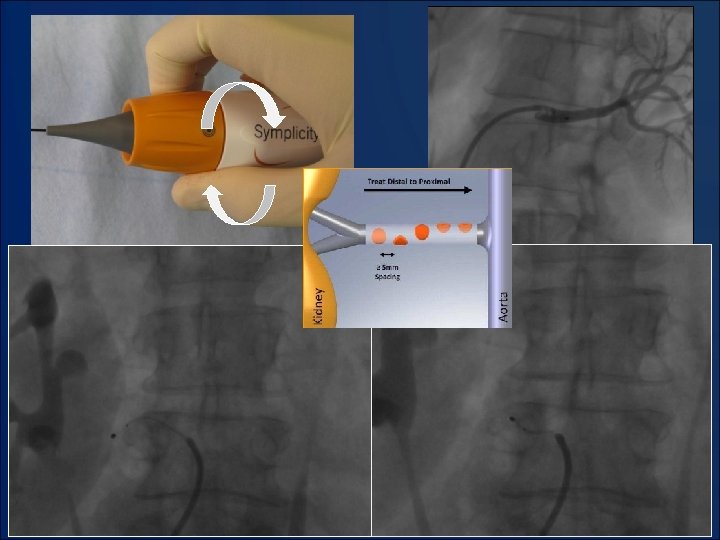

Система катетерной денервации Symplicity Catheter System • Катетер-электрод специальной формы с управляемым дистальным сегментом • Генератор электромагнитного излучения, позволяющий наносить радиочастотные импульсы с максимально эффективной и безопасной частотой • Возможность использования стандартной эндоваскулярной техники доступа • Продолжительность процедуры 40 минут

РДН: позиционирование зонда в просвете почечной артерии

Этапы РДН левой почечной артерии больной М.

РДН больной М. : позиционирование зонда в просвете основной артерии

РДН больной М. : позиционирование зонда в просвете добавочной артерии